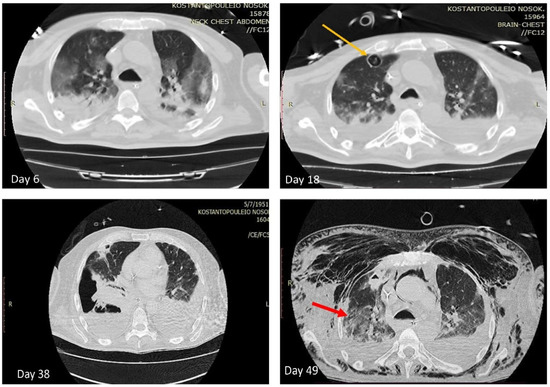

| 18th | CT scan | three cavitary lesions with diameter up to 2.2 cm at upper and middle lobe of the right lung | Voriconazole+ liposomic amphotercinB+ meropenem+ colistin |